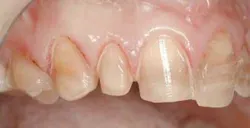

Upon anesthetizing the patient, I decided to remove the old veneers to observe the underlying teeth. I was able to observe the old preparations and the actual color of the teeth. This information will help me with my new preparations (Fig. 6).

null

We found some severely tetracycline-stained teeth that had hardly any preparation. The result was thick teeth (Fig. 7). This is the main reason the ceramist was not able to correct many of the nuances of the smile design we discussed earlier. Adequate preparation is the only way to obtain a fantastic result.